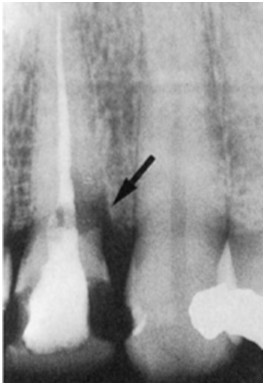

Do gabinetu stomatologicznego zgłosiła się pacjentka lat 35. W związku z zakończonym leczeniem ortodontycznym i planowanym wybielaniem przebarwionego siekacza szczęki oraz utratą wypełnienia wykonano rtg. Badaniem wewnątrzustnym stwierdzono prawidłowy przebieg linii dziąsła, brak ubytków niepróchnicowego pochodzenia oraz obecne ubytki na powierzchni mezjalnej i dystalnej w zębie 11. Zauważono też różowe przebarwienie w okolicy szyjki zęba 11, a w wyniku zgłębnikowania stwierdzono poddziąsłowo obecność tkanki ziarninowej. Postaw diagnozę zmiany zaznaczonej na rtg strzałką:

Pytanie 23